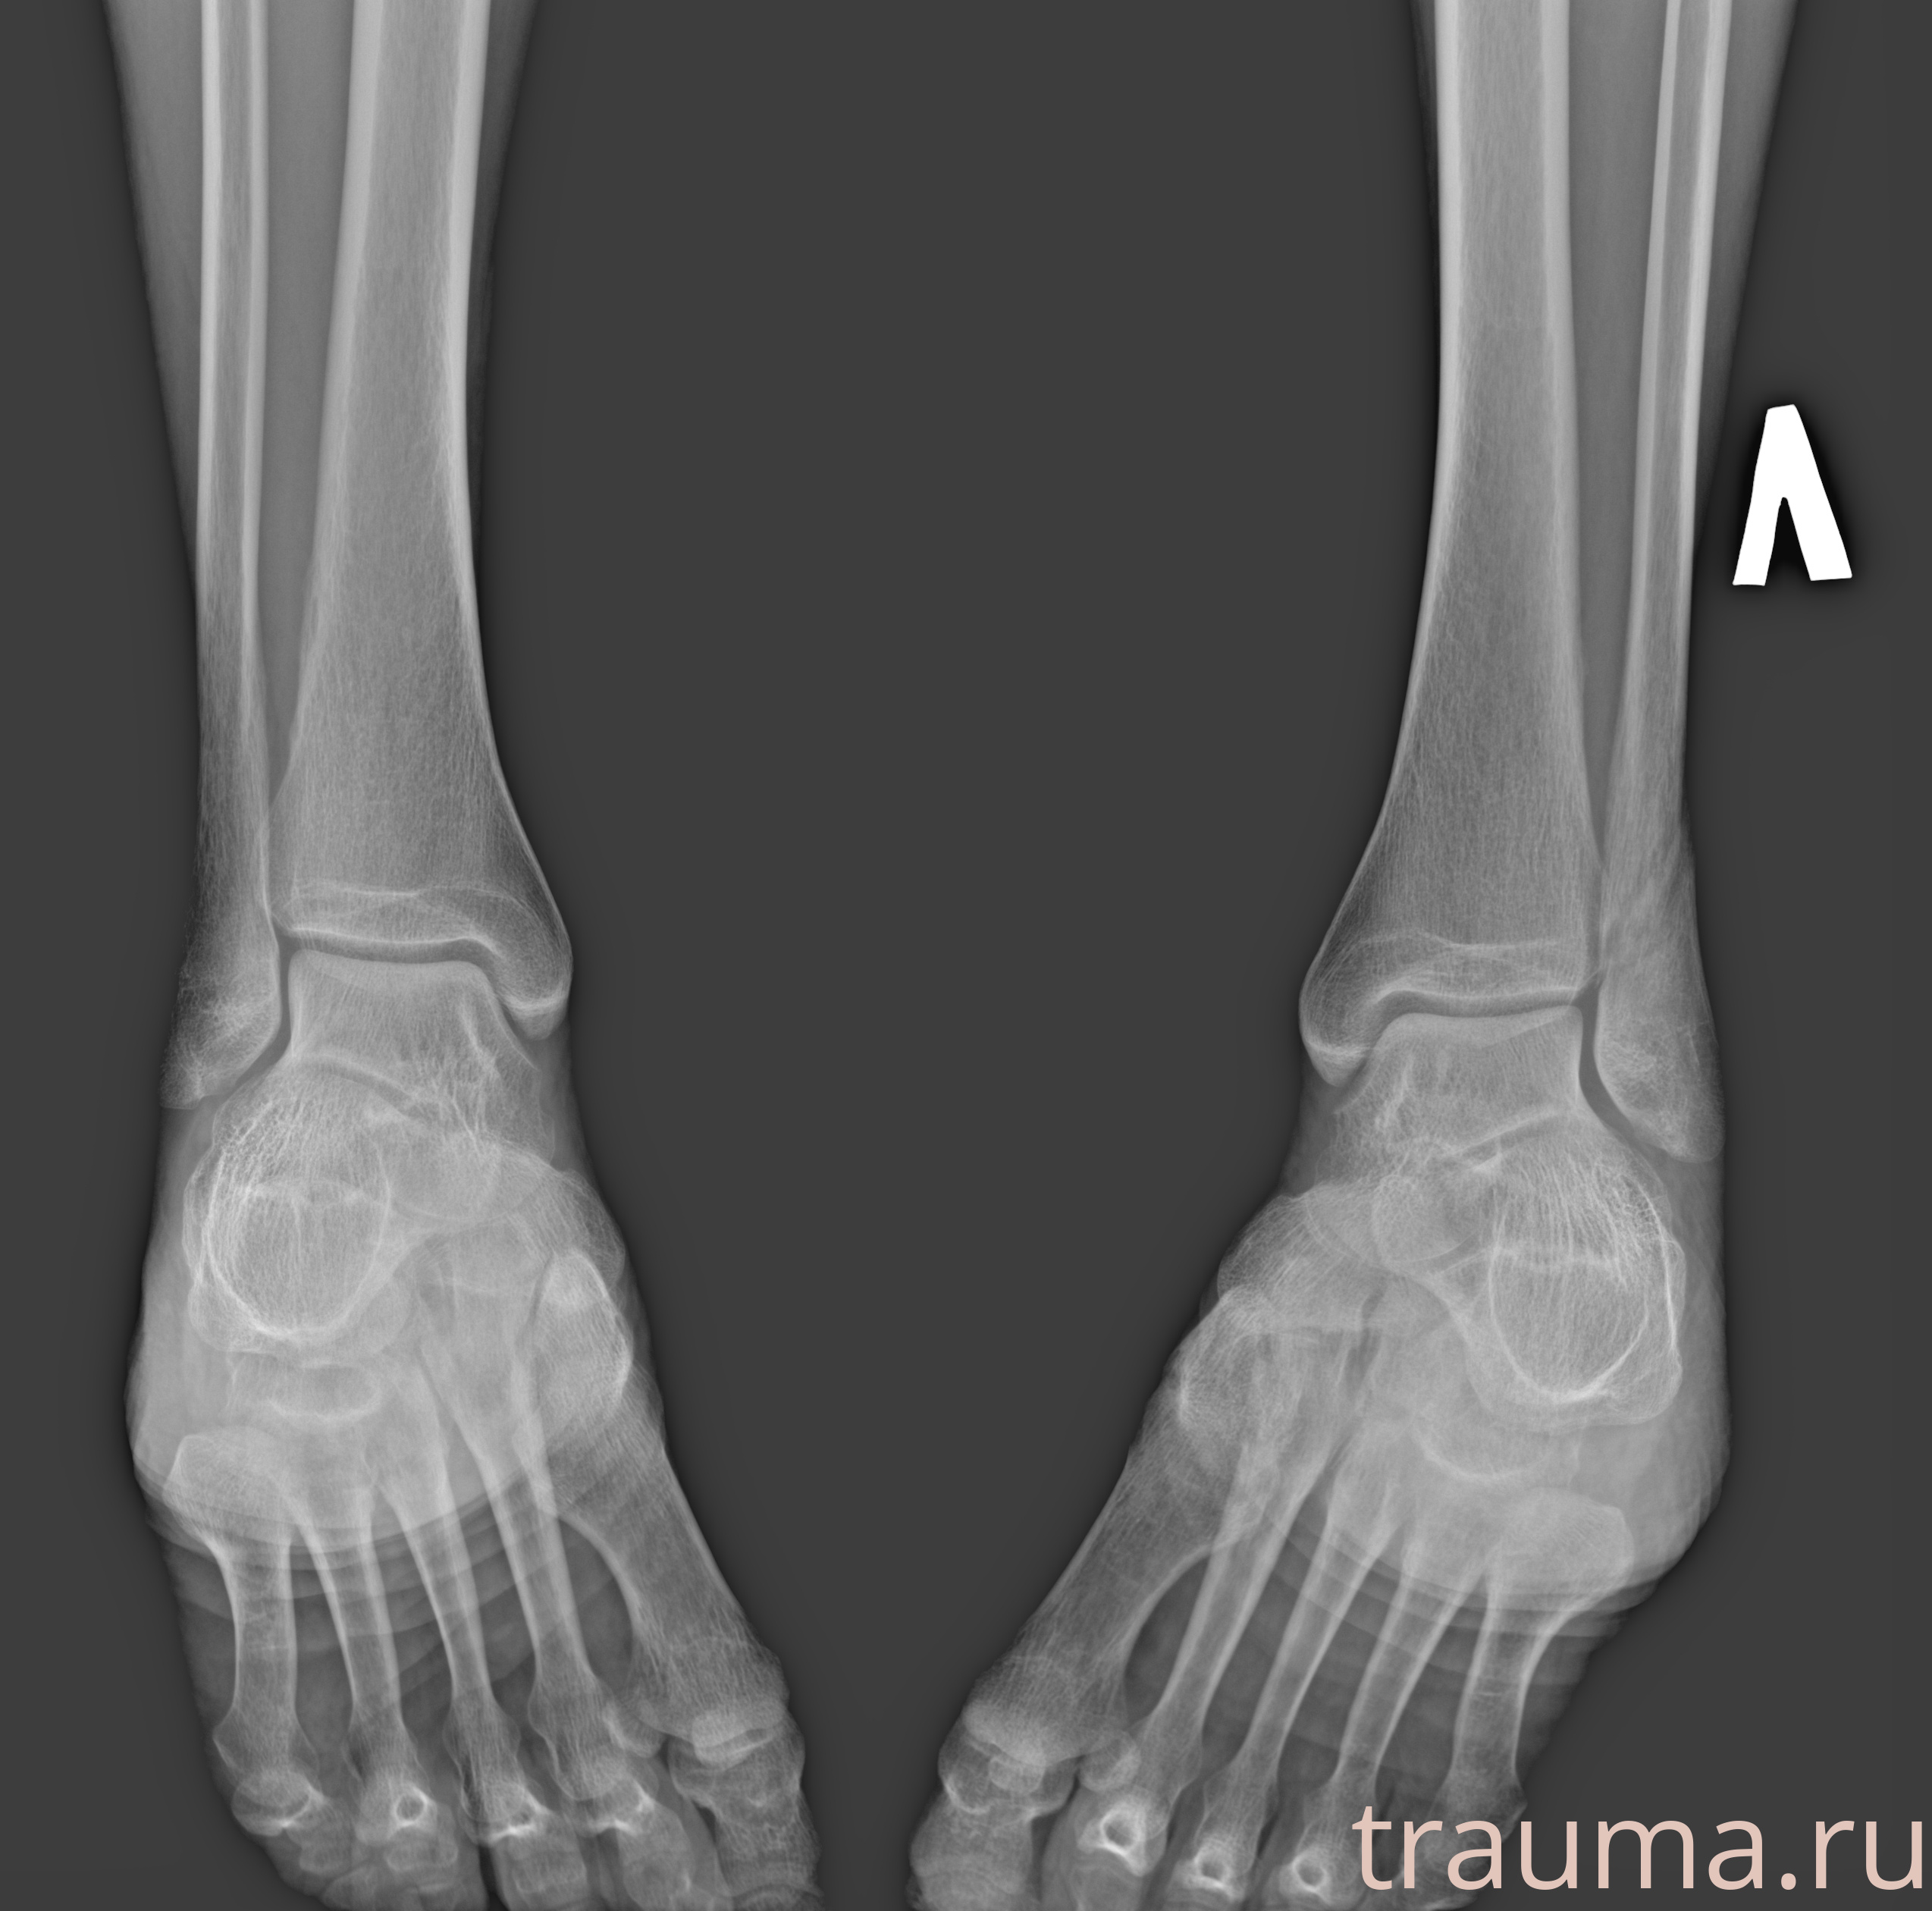

Рентгенограммы

Рентген на дому: по вашему адресу приезжает врач-рентгенолог, травматолог-ортопед с мобильным рентгеновским аппаратом, проводит диагностику травмы или заболевания, делает необходимые рентгенограммы, дает рекомендации по дальнейшему лечению. Получить качественные снимки в домашних условиях возможно благодаря уникальной методике, разработанной МосРентген Центром для института  Склифосовского